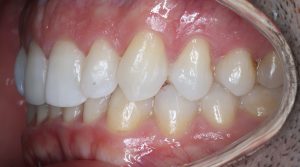

FULL

35 Semanas de tratamiento

37 Semanas de tratamiento